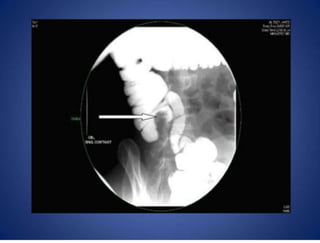

• Barium study Xray (barium enema or barium follow through x-

ray)

— Pulled up caecum, conical caecum, pulled down hepatic

flexure

— Obtuse ileocaecal angle; straightening (Goose neck)

— Steirlin sign: Hurrying of barium due to rapid flow and lack

of barium in inflamed site

— Fleischner sign (Inverted umbrella sign): Narrow ileum

with thickened ileocaecal valve

— Napkin leisons- ulcers and strictures in the terminal ileum